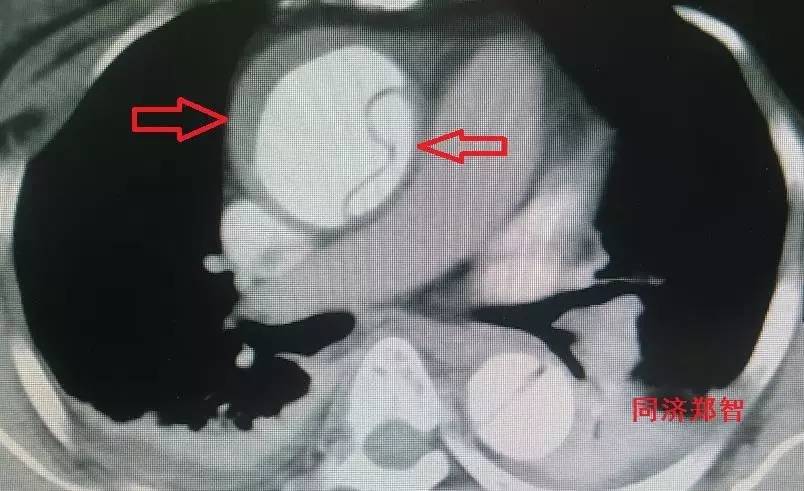

胸降主动脉穿透性溃疡合并壁间血肿(图6),心底层面红箭头所示。

图6